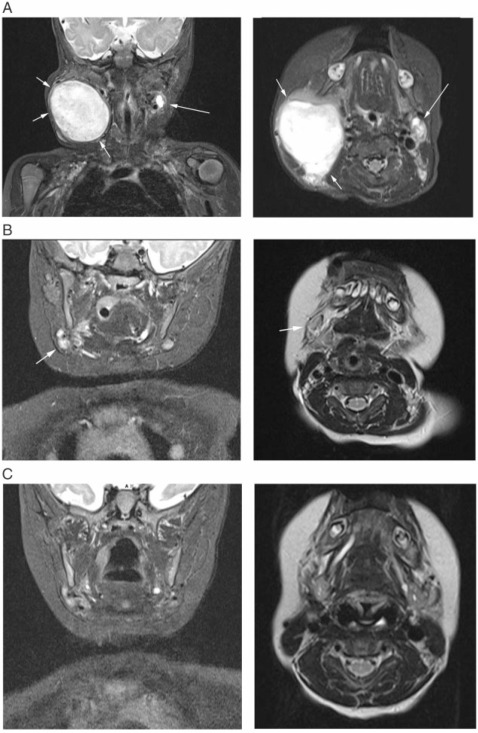

在获得知情同意后,对患者进行筛查以确认其是否合格。MRI筛查证实疾病进展,右侧宫颈指数病变面积为5.5×4.5×4.4 cm(约55cm³;图2 A)。在3.5个月大时开始每日接受口服拉罗替尼的门诊治疗,剂量为100 mg / m 2体表面积,每天两次,对应于1.5 ml 拉罗替尼 20 mg / ml溶液,每天两次,开始于3.5个月大(周期1天1; C1D1)。

图2:在冠状和平面磁共振成像时(A)在筛查时,(B)在治疗的第56天和(C)在治疗的第112天时观察到的右颈病变的最大直径。

父母注意到在4天之内肿瘤的发生了变化,这一点在下一次C1D8诊所就诊时得到了证实,当时的病灶表现为更柔软,触诊时活动性更强,尺寸减小了。在接下来的几天和几周内,肿瘤继续快速消退(图1 B–D)。在接受拉罗替尼治疗(C3D1)第56天进行的首次预定对照MRI检查中,剩下的唯一异常是孤立的右颈淋巴结略微肿大,其大小为1.2×1.2×0.8 cm(约0.6cm³;图2 B) 。根据《 1.1版实体肿瘤的反应评估标准》中的淋巴结反应,其中在垂直于最长直径的轴上测量目标结点。相当于完全缓解(CR)。完全缓解在C5D1的第二次对照MRI上得以维持,先前描述的淋巴结现在完全正常(图2 C),最后一次在C18D1上随访(拉罗替尼开始后16个月)。